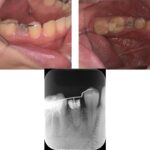

精密根管治療により、

歯を残せる可能性を最大限に

肉眼では見えない細かな部分まで拡大して確認できるため、削りすぎを防ぎ、再発リスクを抑えた質の高い治療が可能です。

当院ではCT・マイクロスコープ・セファロなどの精密検査機器を活用し、歯を残すための選択肢をできる限りご提案します。

歯髄温存治療(MTA)や歯冠長延長術、矯正的挺出など、専門的な治療にも対応。